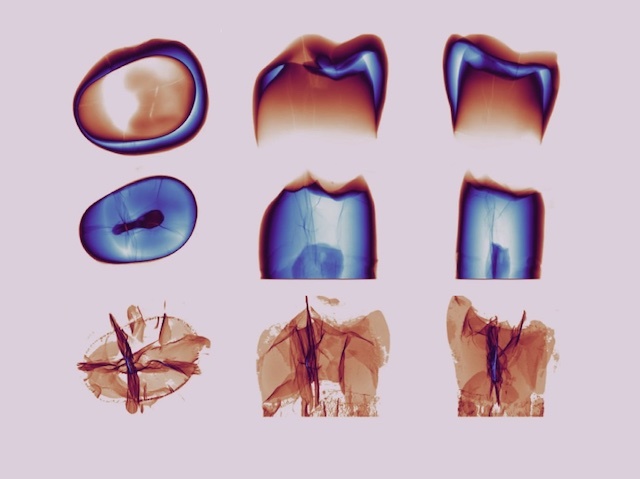

Cracking Teeth

Networks of microcracks in teeth may play a role in protecting tooth integrity

Take a look at smiling photos of yourself and you won’t spot these but they’re there. Microcracks (MCs). These tiny cracks in the hard outer coating of your teeth (enamel) develop with age. How do they affect tooth structure and integrity? Researchers investigate using X-ray micro-computed tomography of four extracted human teeth. Image processing using specific algorithms allowed the team to create 3D images of the density of the enamel (top row) and softer inner tissue (dentine, middle row), as well as MCs (bottom row) from different angles (left to right). This revealed an intricate star-shaped network of MCs that weren’t limited to the enamel but passed through into the dentine along two almost perpendicular planes. These healthy teeth nonetheless retained their structural integrity. MCs may therefore be involved in protecting tooth integrity from the strong forces applied to teeth daily. More research is needed to uncover how.